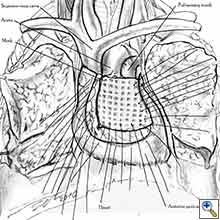

Pericardial reconstruction after anterior mediastinal tumor resection

Some pericardial defects resulting after partial pericardiectomy for invasive anterior mediastinal masses need pericardial reconstruction (Figures 4a-c). This is not the case for small pericardial defects, but large and lateral defects require reconstruction, especially if a lung resection has been performed. In the case of pericardiectomy with pneumonectomy, the postpneumonectomy space plays an important role in the pathogenesis of cardiac herniation. En bloc resection of a mediastinal tumor, the pericardium and the lung increases the risk of herniation in a similar fashion. In the absence of a lung resection, lung atelectasis can also increase this risk. Following complex resections requiring vascular resection followed by reconstruction, the reconstruction can stabilise the vascular prosthesis and prevent it from kinking (Figure 4c). Another potential advantage of pericardial reconstruction is that in the event of a re-do sternotomy, the risk of cardiac laceration is reduced because it prevents sternal-cardiac adhesions from forming [5]

Video 1 depicts a pericardial reconstruction with Marlex after a right completion pneumonectomy with pericardiectomy for lung adenocarcinoma (see also Figure 1). The technique of pericardial reconstruction after the resection of invasive mediastinal tumours is illustrated in Figures 8a-c). Video 2 depicts a pericardial reconstruction with Mersilene mesh after the resection of a malignant thymoma invading the anterior pericardium (see also Figure 4b). The technique of right pericardial reconstruction after extrapleural pneumonectomy is illustrated in Figures 9a and 9b). Video 3 depicts a pericardial reconstruction using Gore-Tex Dual Mesh after a left extrapleural pneumonectomy (see also Figure 3). Care must be taken to prevent constriction (Figure 10).

- The pericardium must be reconstructed in a geometric, tridimensional fashion to avoid constriction (Figures 10a, 10b).

- In the case of anterior pericardioplasty, care must be taken to ensure that the mesh does not constrict depressible vascular structures such as the superior vena cava and the pulmonary trunk.